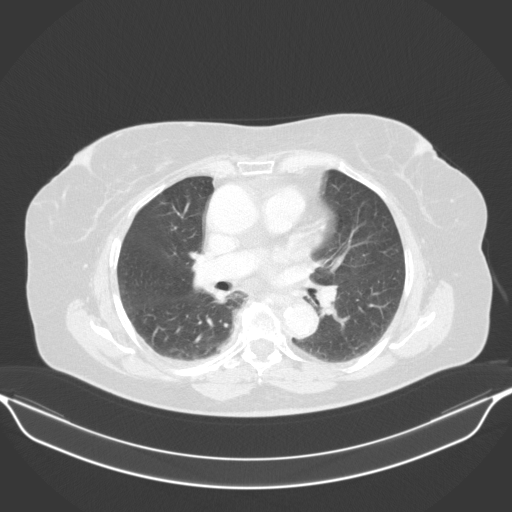

Original VENOUS CT scan

Full window (WL 1023.5, WW 4095 β†’ Low βˆ’1024, High +3071)

Lung window (WL -600, WW 1500 β†’ Low βˆ’1350, High +150)